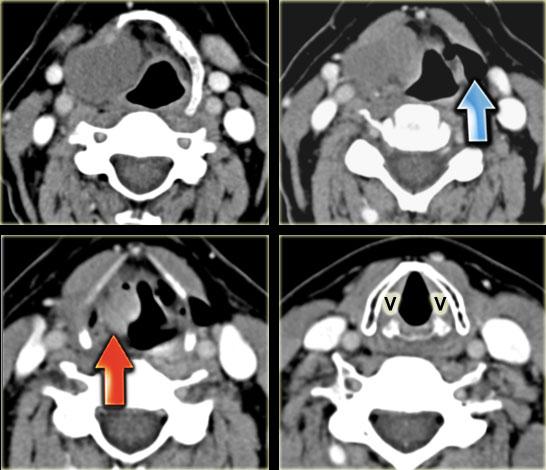

TRÁI: Hình CT mặt phẳng vành qua thanh quản với giải phẫu bình thường: dây thanh giả (F), dây thanh thật (T) và buồng thanh quản ở giữa (V). PHẢI: Túi thoát vị thanh quản thứ phát trong và ngoài chứa dịch do khối u nhỏ ngấm thuốc ở buồng thanh quản (T) gây tắc nghẽn buồng thanh quản. Bên trái là túi thoát vị thanh quản nguyên phát trong và ngoài chứa khí.

Cơ chế hình thành túi thoát vị thanh quản

Buồng thanh quản (v) là khe hở dạng khe giữa dây thanh giả và dây thanh thật (hình ngoài cùng bên trái).

Đây là mốc giải phẫu phân chia vùng trên thanh môn và thanh môn.

Buồng thanh quản kéo dài sang bên và sau đó lên trên vào khoang cạnh thanh môn.

Khi lỗ mở của buồng thanh quản bị khối u tắc nghẽn hoàn toàn, niêm mạc trong khoang cạnh thanh môn tiếp tục tiết dịch.

Điều này dẫn đến túi thoát vị thanh quản bên trong chứa dịch.

Cuối cùng, khoang cạnh thanh môn bị lấp đầy và túi thoát vị thanh quản bên trong sẽ trở thành bên ngoài bằng cách lan ra ngoài thanh quản qua màng giáp móng.

Khi lỗ mở của buồng thanh quản bị tắc nghẽn một phần, cơ chế van áp lực có thể tạo ra túi thoát vị thanh quản bên trong chứa khí, và cuối cùng có thể trở thành bên ngoài (hình bên phải, mũi tên đỏ).